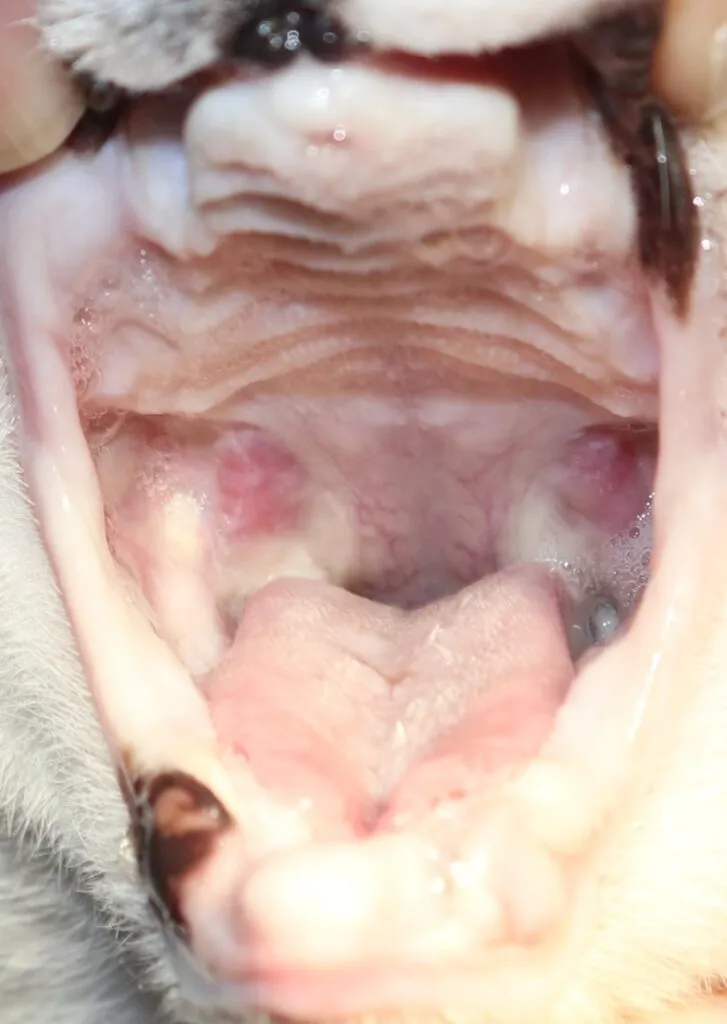

9 歳の猫ちゃん(約5 kg)の口内炎治療🦷

Before

処置中

After

コメント:

この子は、重度の口内炎で食事がとれず、よだれが多い状態でした。

口内炎の治療は大きく分けて内科療法と外科療法があります。

内科療法では改善が乏しかったため、麻酔をかけ全ての歯の抜歯をおこないました。

小さくて見えにくかった小さな歯もマイクロスコープにより認識しやすくなりました。

処置後は内科療法を継続し、1年後には炎症もだいぶ引いたのが分かります。

現在は、痛みやよだれもなくご飯を食べられるようになりました🐱